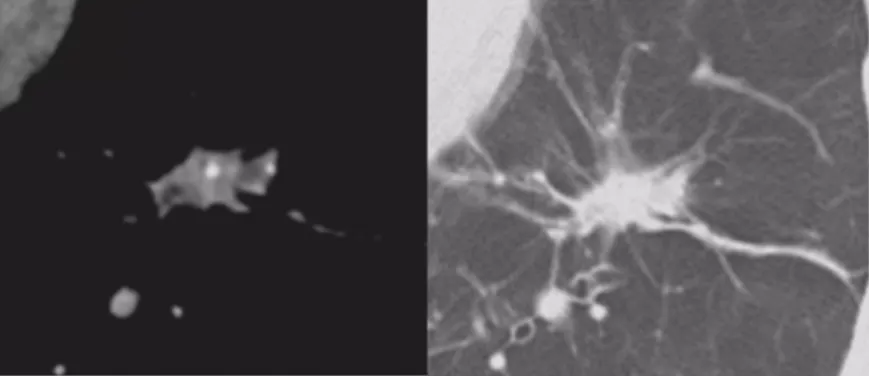

内部特征:燕麦圈征(开放支气管征)

还有非常容易被大家忽略的一个特点(如上图所示),文献上把这个病灶称为燕麦圈征,这不是个好征象。由开放气道周围的肿瘤细胞或非肿瘤细胞增生所致,多见于肺腺癌和肺朗格汉斯细胞组织细胞增多症。尤其是女性病人出现这种征象的概率比较高,出现之后一定要手术。